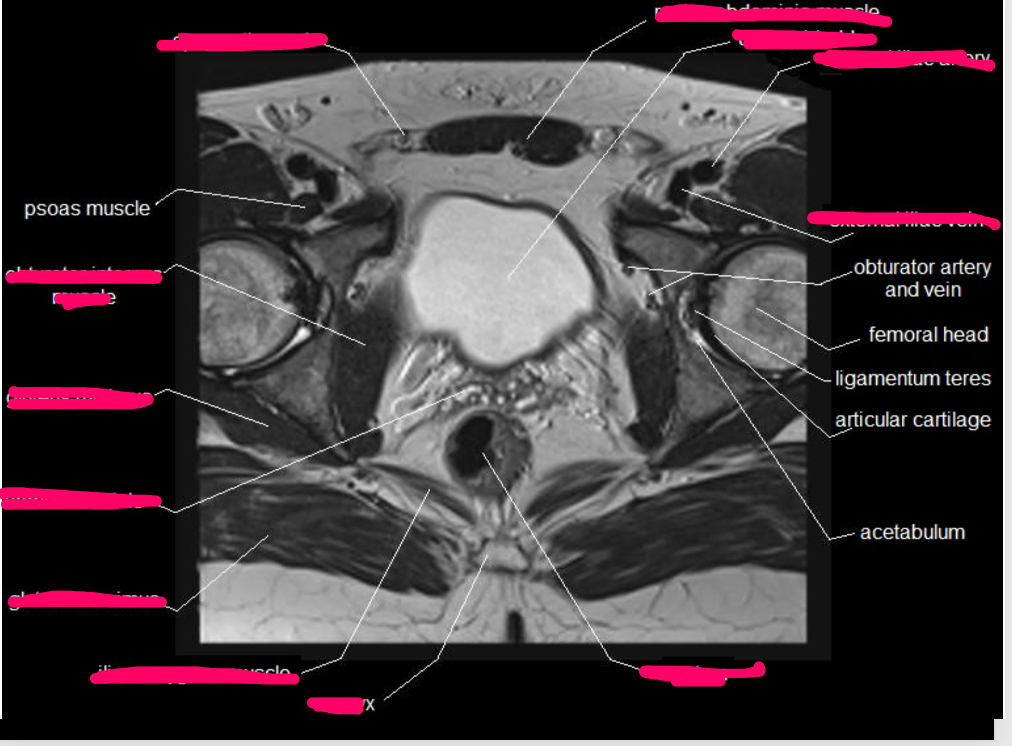

Name the imaging modality & the plane

Axial female MRI, pelvis